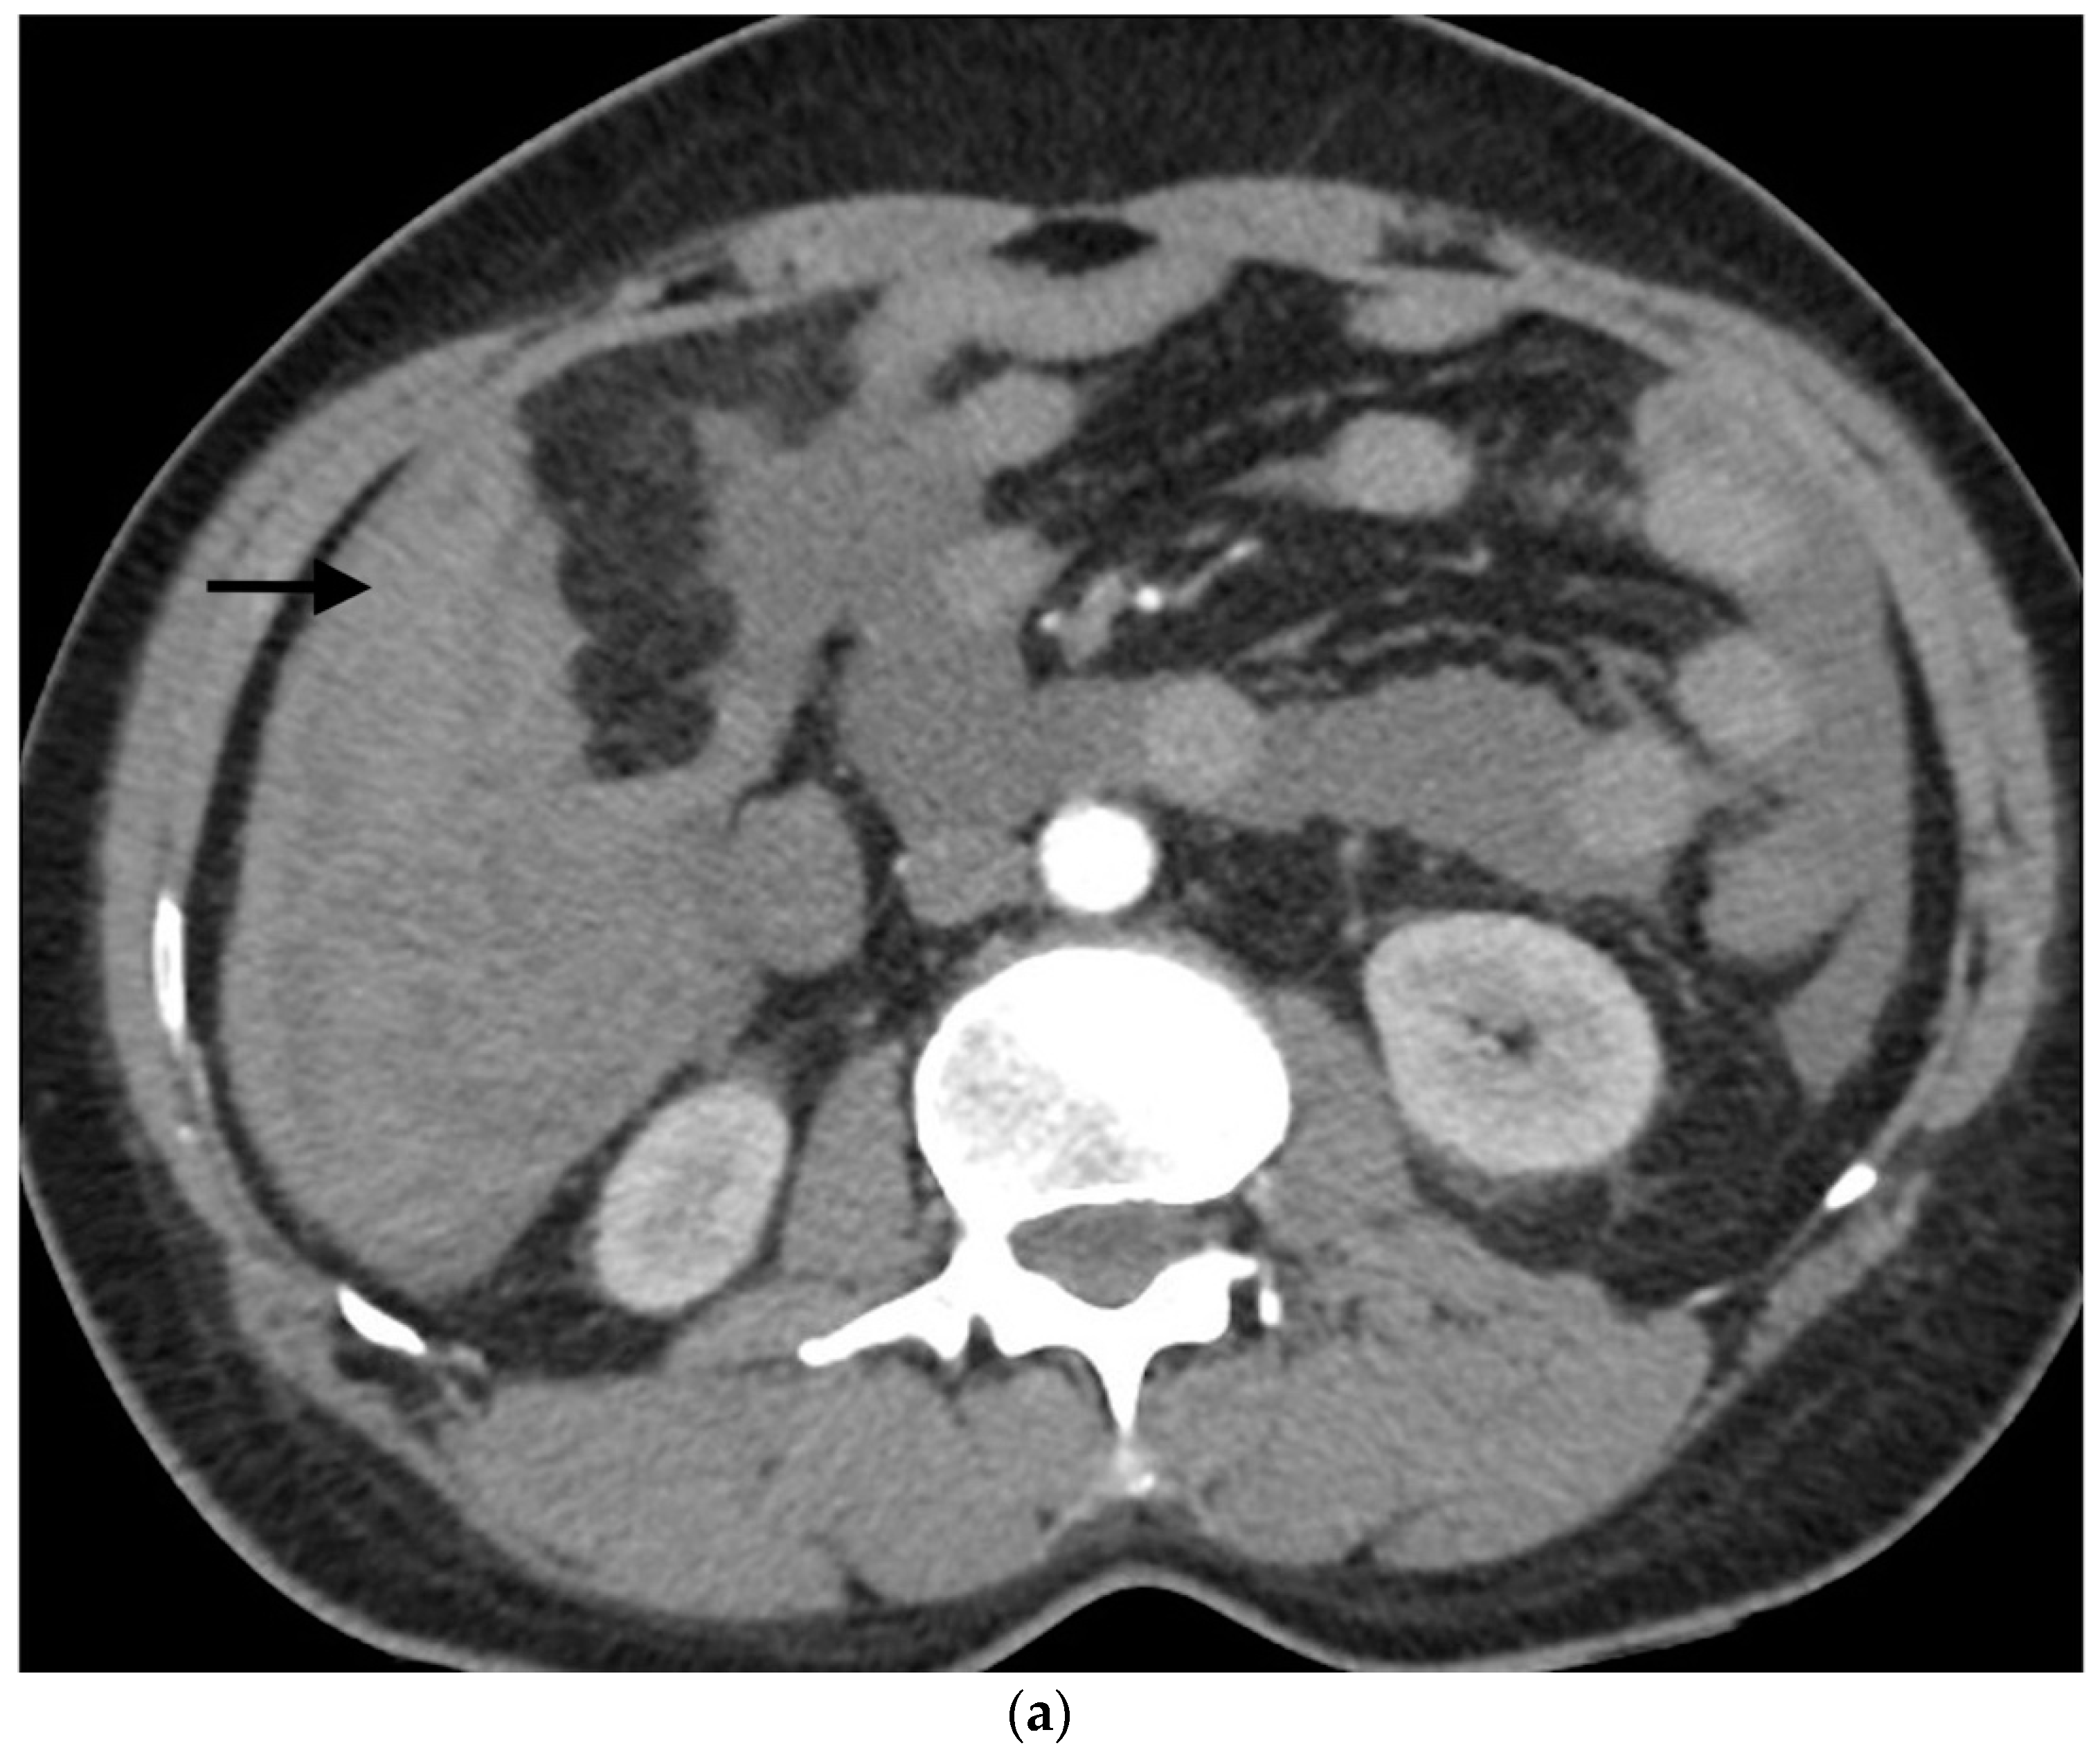

- Sandomenico, F.; Arpaia, V.; De Rosa, F.; Catalano, O.; Buonaiuto, R.A.; Notarangelo, M.; Iovino, M.; Giovine, S.; Brunetti, A.; Scaglione, M. Spontaneously ruptured hepatocellular carcinoma: Computed tomography-based assessment. Diagnostics 2023, 13, 1021. [Google Scholar] [CrossRef]

- Singhal, M.; Sinha, U.; Kalra, N.; Duseja, A.; Khandelwal, N. Enucleation sign: A computed tomographic appearance of ruptured hepatocellular carcinoma. J. Clin. Exp. Hepatol. 2016, 6, 335–336. [Google Scholar] [CrossRef] [PubMed]

- Kim, H.C.; Yang, D.M.; Jin, W.; Park, S.J. The various manifestations of ruptured hepatocellular carcinoma: CT imaging findings. Abdom. Imaging 2008, 33, 633–642. [Google Scholar] [CrossRef] [PubMed]